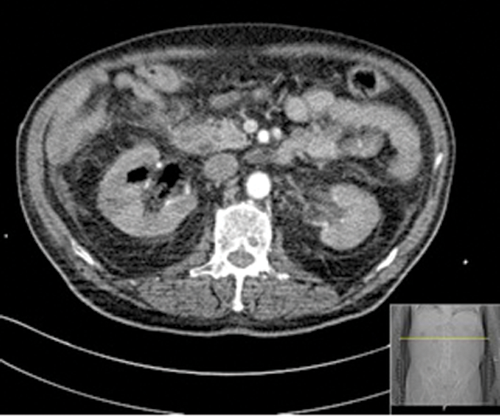

Figures 1: Patient A. Air in the collecting system extending into renal parenchyma.

Figures 2: Patient B. Emphysematous pyelonephritis GM.